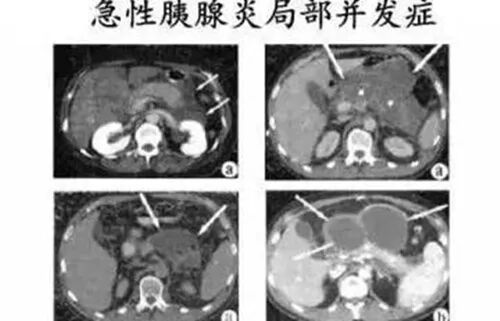

总之,越早使用干细胞治疗效果越好。早期治疗可以有效抑制炎症引起的多器官损伤,胰腺炎是一种炎症性疾病,炎症反应是重症胰腺炎早期重要的病理变化,过度的炎症反应引起的炎症反应综合征是导致器官损伤,甚至早期死亡的主要原因。所以,尽早使用干细胞治疗可以有效的阻止胰腺炎的病程进展,更早的恢复身体健康。